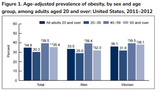

>almost 70 PERCENT of women are OBESE